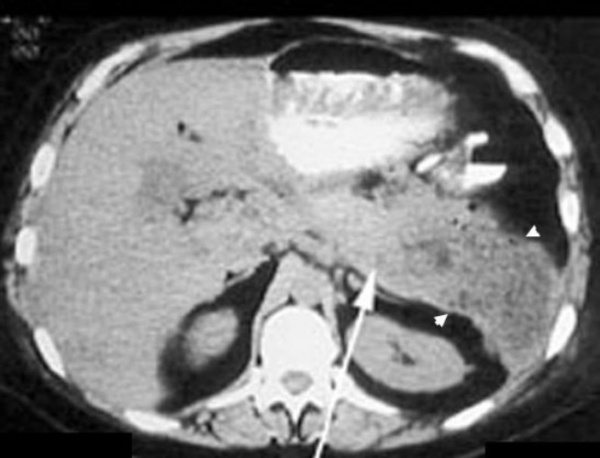

МСКТ и УЗИ брюшной полости позволяют подтвердить наличие жидкости, гноя и газа в брюшной или плевральной полости, изменение положения и состояния прилежащих внутренних органов (например, деформацию желудка, смещение продольной оси сердца и др.). Диагностическая пункция абсцесса допустима лишь во время операции.

КТ органов брюшной полости. Диффузно увеличенная поджелудочная железа. Большая стрелка указывает на тело поджелудочной железы, маленькие стрелки - на абсцесс, расположенный в хвосте поджелудочной железы.